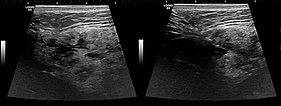

Ultrasound images (automatically assembled 2D B-mode images) before sclerotherapy. The initially hypoechoic cavities of the venous malformation are occluded by the inflammation induced by sclerotherapy.